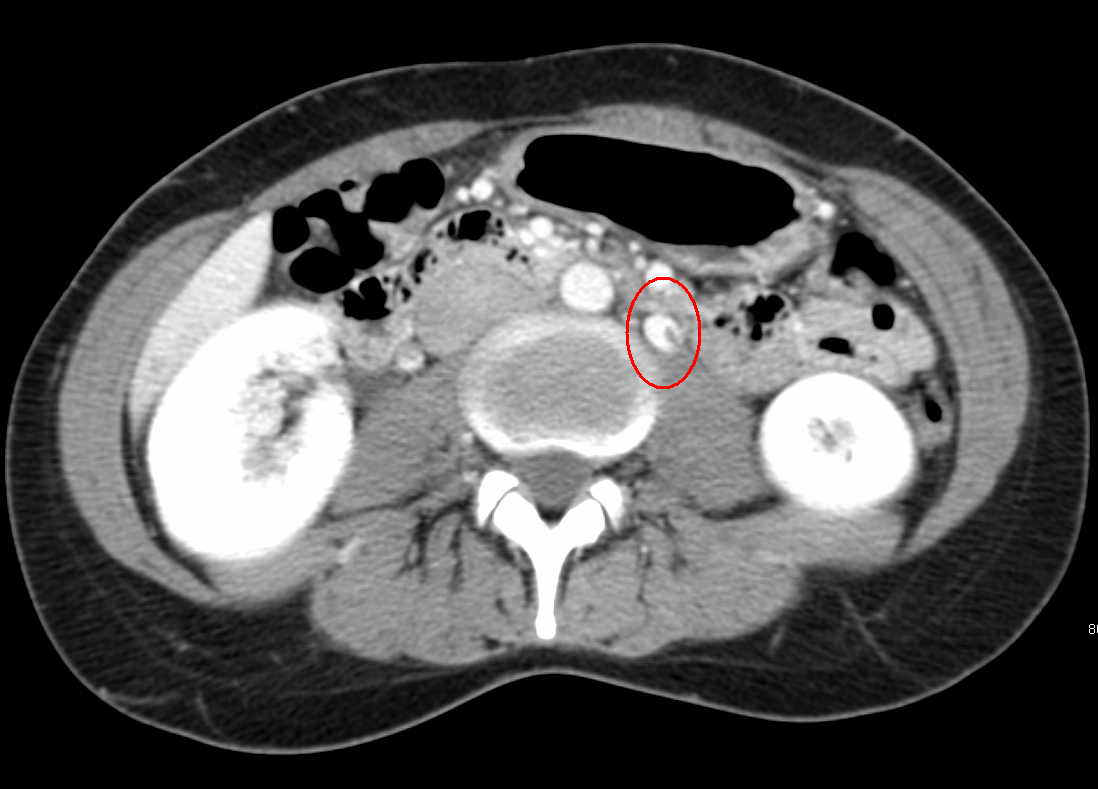

Figure I from Acute Pulmonary Thromboembolism in a Patient with Nutcracker Syndrome Thrombosis Although uncommon, it is an important. Nutcracker syndrome (ncs) describes left renal vein compression between the superior mesenteric artery and the aorta. Nutcracker syndrome can result in significant morbidity, including chronic renal disease and venous thrombosis.[4] nutcracker. The optimal treatment includes open decompression of the left renal vein with renal vein transposition or gonadal vein transposition, with or without concomitant.. Nutcracker Syndrome Thrombosis.

Figure 1 from RENAL VEIN THROMBOSIS DUE TO POSTERIOR NUTCRACKER Nutcracker Syndrome Thrombosis Nutcracker syndrome can result in significant morbidity, including chronic renal disease and venous thrombosis.[4] nutcracker. Although uncommon, it is an important diagnosis due to the important morbidity associated with it, including the risk of chronic kidney disease. Although uncommon, it is an important. Orthostatic proteinuria has also been. Nutcracker syndrome (ncs) describes left renal vein compression between the superior mesenteric. Nutcracker Syndrome Thrombosis.